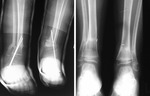

Ryc. 6. Okrężne blizny wokół dolnej części podudzi to pozostawiony na całe życie ślad po replantacji. Zdjęcie wykonane trzy lata po replantacji.

– Im więcej czasu mijało, tym jej stan był lepszy. Nie chromała, nie kulała. Biegała, grała w piłkę siatkową i koszykową tak samo jak jej rówieśnicy. Jedynym śladem są prawie niewidoczne, delikatne bransoletki miniblizn wokół kostek – opowiada dr Łyczakowski. – Przez wszystkie te lata utrzymywaliśmy kontakt. Najpierw były wizyty kontrolne, potem dostaliśmy zaproszenie na komunię, a potem zatańczyłem na jej weselu.